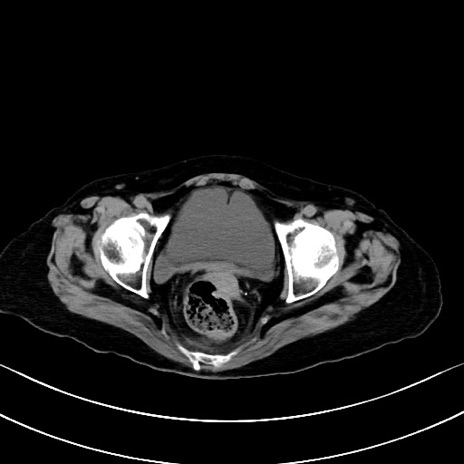

冠状断像